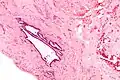

| High magnification micrograph of endosalpingiosis, showing the characteristic cystic spaces lined by a simple epithelium with cilia. H&E stain. | |

It is characterized by cysts with tubal-type epithelium (e.g. ciliated epithelium) surrounded by a fibrous stroma. It is not often associated with hemorrhage.